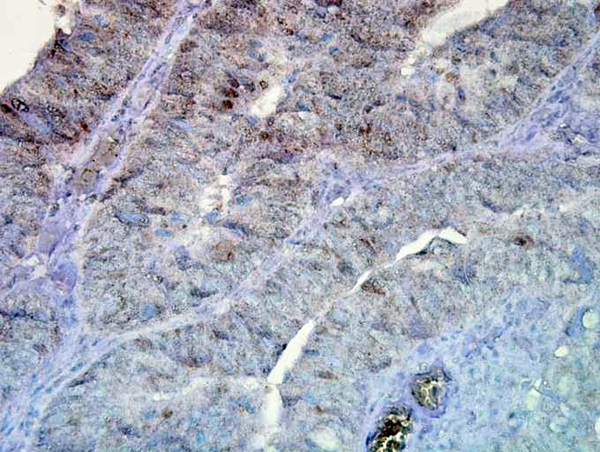

IHC (Immunohiostchemistry)

(Immunohistochemistry analysis using Mouse Anti-Hsp90 Monoclonal Antibody, Clone D7alpha. Tissue: inflamed colon. Species: Mouse. Fixation: Formalin. Primary Antibody: Mouse Anti-Hsp90 Monoclonal Antibody at 1:100000 for 12 hours at 4 degree C. Secondary Antibody: Biotin Goat Anti-Mouse at 1:2000 for 1 hour at RT. Counterstain: Mayer Hematoxylin (purple/blue) nuclear stain at 200 ul for 2 minutes at RT. Localization: Inflammatory cells. Magnification: 40x. Inflammatory cells.)

IHC (Immunohistochemistry)

(Immunohistochemistry analysis using Mouse Anti-Hsp90 Monoclonal Antibody, Clone D7alpha. Tissue: colon carcinoma. Species: Human. Fixation: Formalin. Primary Antibody: Mouse Anti-Hsp90 Monoclonal Antibody at 1:100000 for 12 hours at 4 degree C. Secondary Antibody: Biotin Goat Anti-Mouse at 1:2000 for 1 hour at RT. Counterstain: Mayer Hematoxylin (purple/blue) nuclear stain at 200 ul for 2 minutes at RT. Magnification: 40x.)